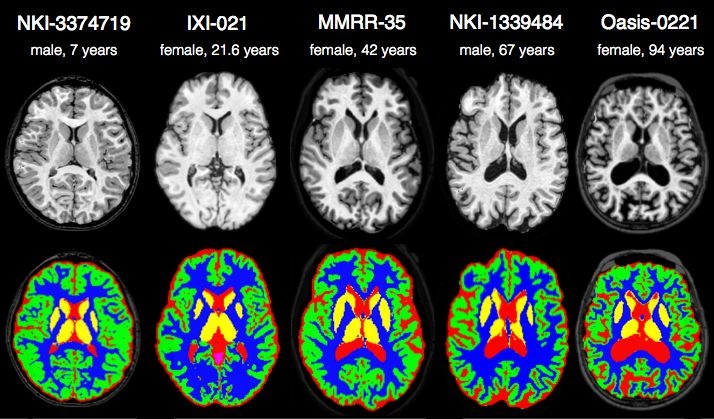

U-Net系列模型在多个图像处理与计算机视觉领域展现出广泛的应用价值,并且其性能特点使其成为诸多领域的关键工具之一。从病理学角度来看,在医学影像分析方面展现出了显著的优势与潜力;尤其是在疾病诊断与治疗方案制定过程中发挥着不可替代的作用。具体而言,在医学影像分析方面,U-Net系列模型能够实现对特定组织或器官的精准检测与分隔,如肿瘤组织、血管网以及单个细胞等;从病理学角度来看,该方法能够实现癌细胞的自动识别与分隔;此外,它还能够在遥感影像分析方面发挥重要作用,能够在遥感影像中识别出建筑群、森林区域以及水域等地物类型;值得注意的是,该方法不仅限于医疗领域的应用,还能够拓展至自然环境下的物体分类任务,例如语义分类与实例分类等场景;值得注意的是,尽管最初是为医学领域的复杂场景设计而生,但该方法经过改进后也能够较好地适应自然环境下的物体分类任务

在图像分割领域中,多模态融合技术旨在通过整合来自不同成像模式和传感器的数据来提升分割的准确性和鲁棒性。各个成像模式能够提取物体的各自特征。其中一种常见的方法是利用光学图像来获取丰富的颜色信息以及纹理细节;而红外图像则对温度变化高度敏感;此外,磁共振成像(MRI)能够呈现软组织内部的结构;计算机断层扫描(CT)则专注于显示骨骼结构以及高密度物质。通过将这些互补的信息结合起来,多模态融合旨在构建一个更加完整、准确且详实的场景表示。